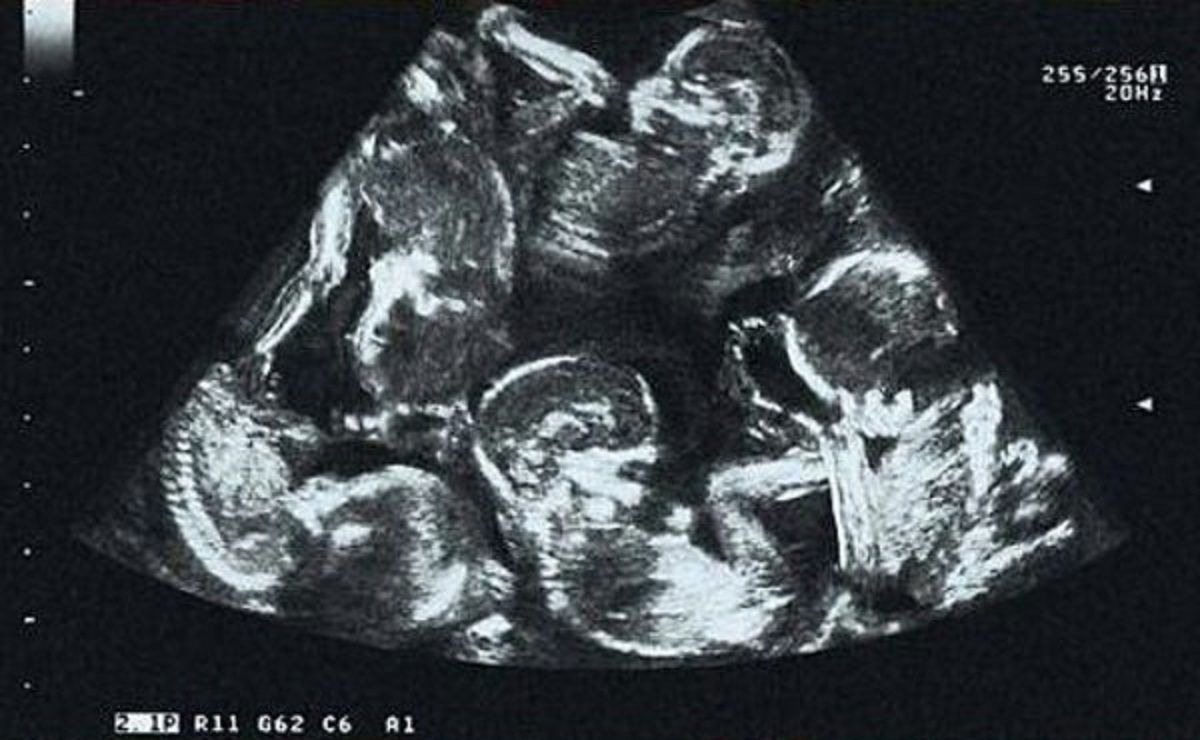

Podczas pierwszego badania USG lekarze stwierdzili, że Alexandra spodziewa się więcej niż jednego dziecka. Para nie była zbyt zaskoczona – w ich rodzinach zdarzały się już bliźnięta i zakładali, że po prostu kontynuują tradycję. Alexandra przygotowała się na bliźnięta, nie zdając sobie sprawy, że los szykuje dla niej znacznie większą niespodziankę.

Kolejna kontrola zszokowała zarówno lekarzy, jak i rodziców. Zamiast dwojga dzieci, było ich czworo. Odkrycie to sprawiło, że wszyscy zaniemówili, ale największa niespodzianka miała dopiero nadejść. Kolejne badanie USG potwierdziło, że Alexandra spodziewała się nie czworga, ale pięciorga dzieci. Ogarnięta emocjami, nie mogła w to uwierzyć.